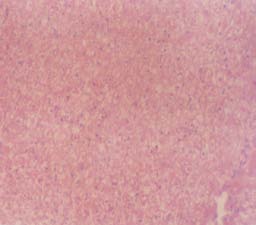

Experimental rabbits were dissected on the 9th day after administration of saponin. The method describe by Patel et al. (2010) was employed for the dissecting. They were killed by chloroform anesthesia and dissected. The small and large intestine, liver and kidneys were removed separately and cut into sections, The sections were fixed directly on a slide, stained with haematoxylin and eosin, examined and photographed.

The effect of saponin on the activity of serum, liver and kidney enzymes in controlled and experimental groups of rabbits is shown in Table 4 indicating the activity of marker enzymes (AST and ALT). Slight differences were observed in the activity of enzymes in all the groups of rabbits tested. The result of the histopathological studies of the liver, kidney and small intestine of treated and untreated rabbits is shown in figs 1, 2 and 3 respectively. The liver, small intestine and kidney of the untreated rabbits showed no visible lesion, but there were sectioning artifacts (figs 1(a), 2(a) and 3 (a)). In the treated liver, there was a mild periportal lymphocytic and histiocytic cellular infiltration (Fig 1b). In the kidney, there are multiple foci of haemorrhages into the intertitium. There were few loci of tubular necrosis and presence of hyaline casts with interstitial cellular infiltration by macrophages (fig 2b), and small intestine of the treated rabbits there were marked hyperplasias of the mucosal layer (Fig 3b).

There was however a gradual reduction of the blood glucose to an insignificant level (p < 0.001) after 9 days. This could be due to constancy of distribution, metabolism and excretion of the saponin (Zhongguo et al., 2005). The presences of transaminase (AST and ALT) are good indices of liver and kidney damage (Nishiura et al., 2005). In this study, saponin did not induce any damage to any of the organs which could be inferred from the normal values of these enzymes. Reduction in the level of AST and ALT is an indication of the stabilization of plasma membranes as well as repair of hepatic tissue damage. This in effect conforms with the commonly accepted view reported earlier by Francis et al. (2002) that serum levels of transaminase return to normal with healing of hepatic parenchyma and the regeneration of hepatocytes. It thus, means that in this study, the saponin therapy did not lead to liver inflammation and/or kidney dysfunction.

The appearance of mild periportal lymphocytic and histiocytic cellular infiltration in the liver of the saponin-treated rabbits is an indication of a cellular immunological response brought about by infiltration of polymorphornuclear leucocytes to the site of infection induced by Salmonella typhi (Pooneh et al., 2010).